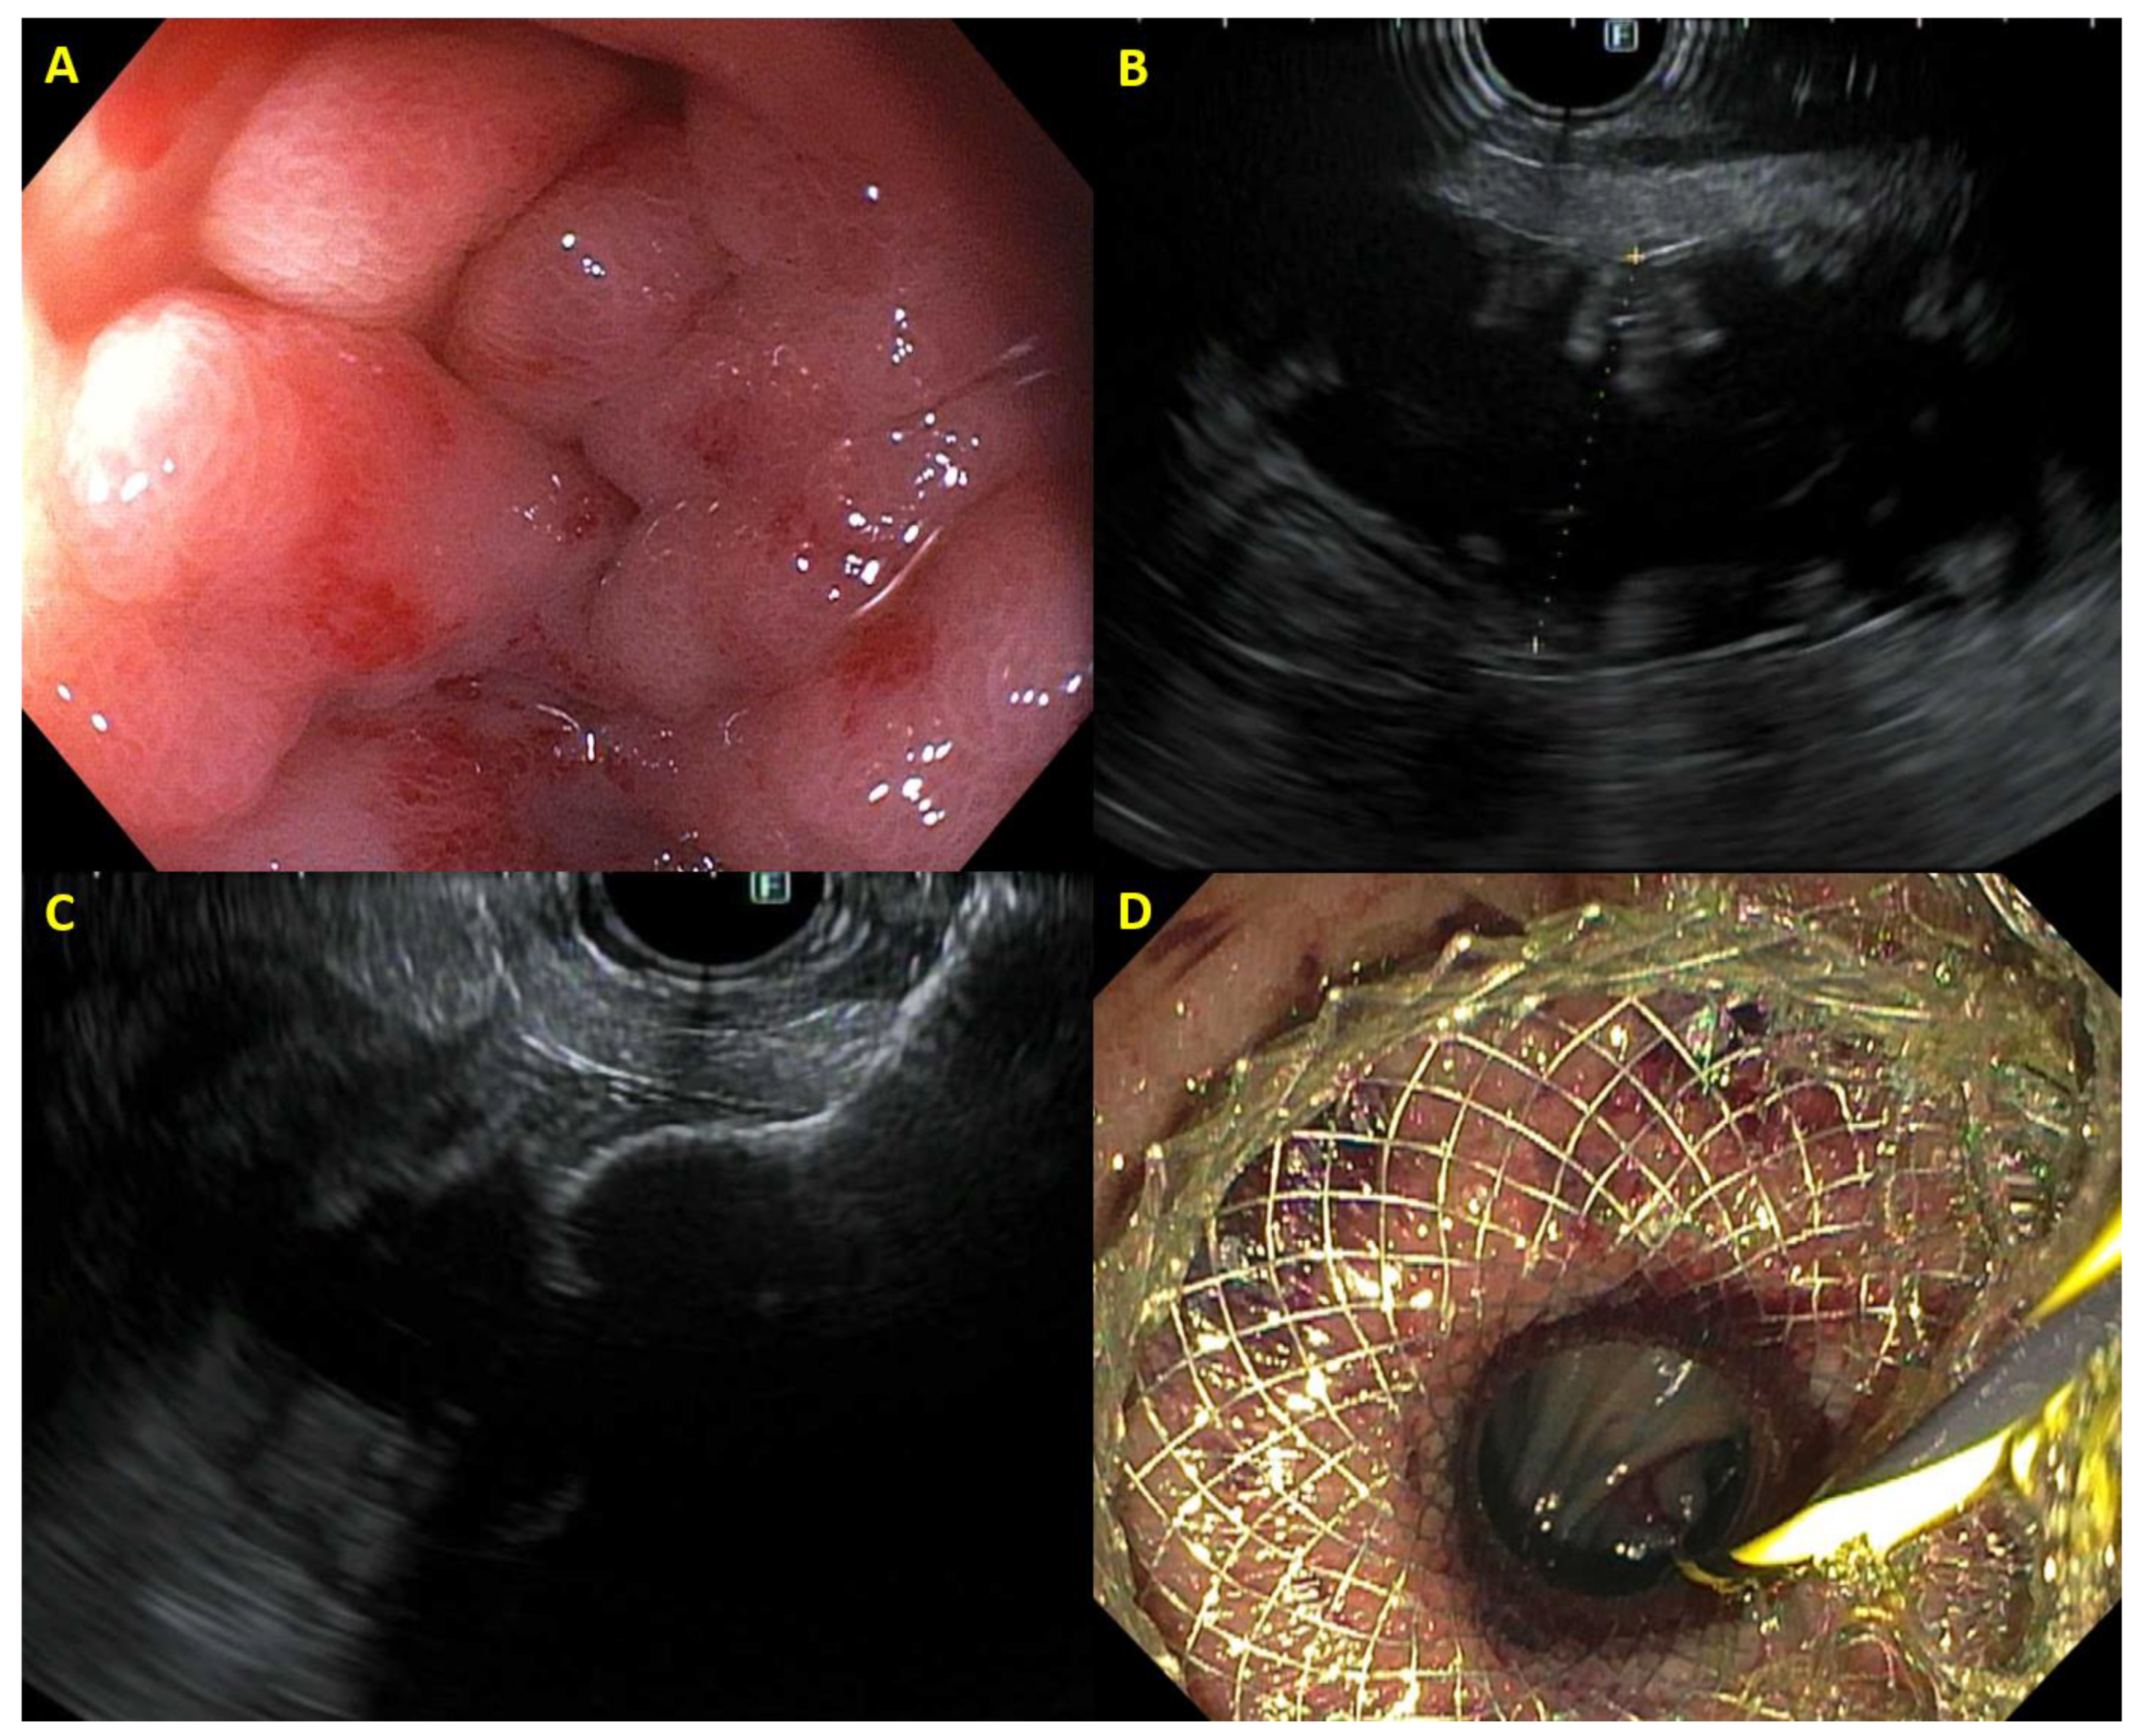

The development of the LAMS and specifically the electrocautery-enhanced LAMS (Hot AXIOS, Boston Scientific, Marlborough, MA, USA; Hot Spaxus, Taewoong Medical, Gimpo, Republic of Korea; Hanarostent Hot Plumber Z-EUS IT, M.I. Tech, Seoul, Republic of Korea) has greatly simplified the process of performing an EUS-CD (Figure 1) [15]. The electrocautery-enhanced LAMS enables the endoscopist to puncture the bile duct and deploy the stent in a single step, not only saving time, but also reducing the risk of adverse events such as bile leakage and infection that can occur when performing the multiple steps required with the traditional EUS-CD. A recent randomized trial involving multiple sites from different continents compared EUS-CD utilizing a LAMS with ERCP for biliary decompression in patients with unresectable malignant distal biliary obstruction (n = 155, 96.1% PDAC) [7]. EUS-CD had a superior technical success rate (96.2% vs. 76.3%) with no difference in 1-year stent patency rates or other adverse events. The mean survival was 232.2 ± 190.9 days with EUS-CD and 202.6 ± 176.3 days with ERCP. As expected, EUS-CD had a significantly shorter procedural time (10 vs. 25 min) than ERCP, highlighting the primary advantages of EUS-CD over ERCP; the ability to perform biliary drainage when the major papilla is inaccessible and quicker procedure times. Another recent multicenter randomized trial from Canada (n = 144) compared EUS-CD with LAMS with ERCP in patients with periampullary cancer (90.3% PDAC—35.2% borderline resectable/locally advanced, 64.8% unresectable) [8]. While there was no difference in technical success rates (90.4% EUS-CD vs. 83.1% ERCP), EUS-CD had a shorter procedure time (14 vs. 23 min) with no difference in adverse events or stent dysfunction. In addition to these trials, several other studies have corroborated the high success rates of using LAMS for EUS-CD. A large retrospective multicenter study (n = 256, 75% PDAC) from Italy examined the use of EUS-CD with LAMS after a failed ERCP, finding a technical success and clinical success rate of 93.3% and 96.2%, respectively [16]. Food occlusion resulting in stent obstruction occurred in 6.7% of patients and bleeding occurred in 1.7% of patients. Another retrospective multicenter study (n = 52, 82.7% PDAC) from France found a technical success rate of 88.5% with a clinical success rate of 100% with a mean procedure duration of 10 min [17]. Long-term adverse events primarily consisted of recurrence of jaundice arising from tumoral obstruction (7.7%) and food occlusion (3.9%). Notably, a recent single-center prospective study (n = 22, 91% PDAC—46% resectable, 27% locally advanced, 27% metastatic) from the Netherlands found that despite high technical and clinical success rates using a LAMS for EUS-CD as the primary biliary drainage strategy, a high proportion of subjects (55%) experienced some degree of stent dysfunction including compression of the LAMS within the bile duct (20%) and food impaction (10%) [18]. The majority of these cases of stent dysfunction were treated successfully with repeat endoscopic intervention.

Figure 1. Example of EUS-guided choledochoduodenostomy with (A) dilated bile duct on EUS, (B) distal flange of lumen-apposing metal stent deployed within the bile duct, (C) proximal flange of lumen-apposing metal stent draining bile in the duodenum, and (D) cholangiogram demonstrating correct placement of choledochoduodenostomy.